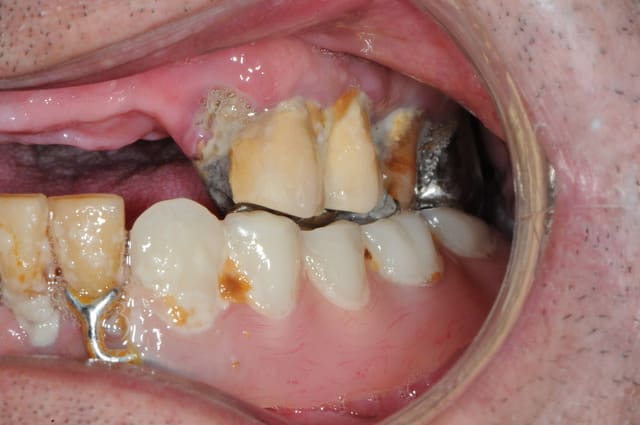

Patient vu en début d'année, parodontite en phase terminale, "monsieur je pense qu'il faudrait vous enlever quelques dents" (voir pano). Lui pas trop pressé apparemment.

Il revient me voir ce mois-ci pour faire sa prothèse. Je lui dit qu'il faut extraire ses dents d'abord.

Il me répond : "ah ben non, elles sont déjà tombées, mais je les garde en bouche ... en attendant!"

Et donc à chaque étape, empreinte, RIM, essayage, je demandais à monsieur d'enlever ses dents, qu'il remettait en place à la fin de la séance.

Du jamais vu pour moi, même si je suis encore jeune dans le métier!!

Fallait que je fasse partager!